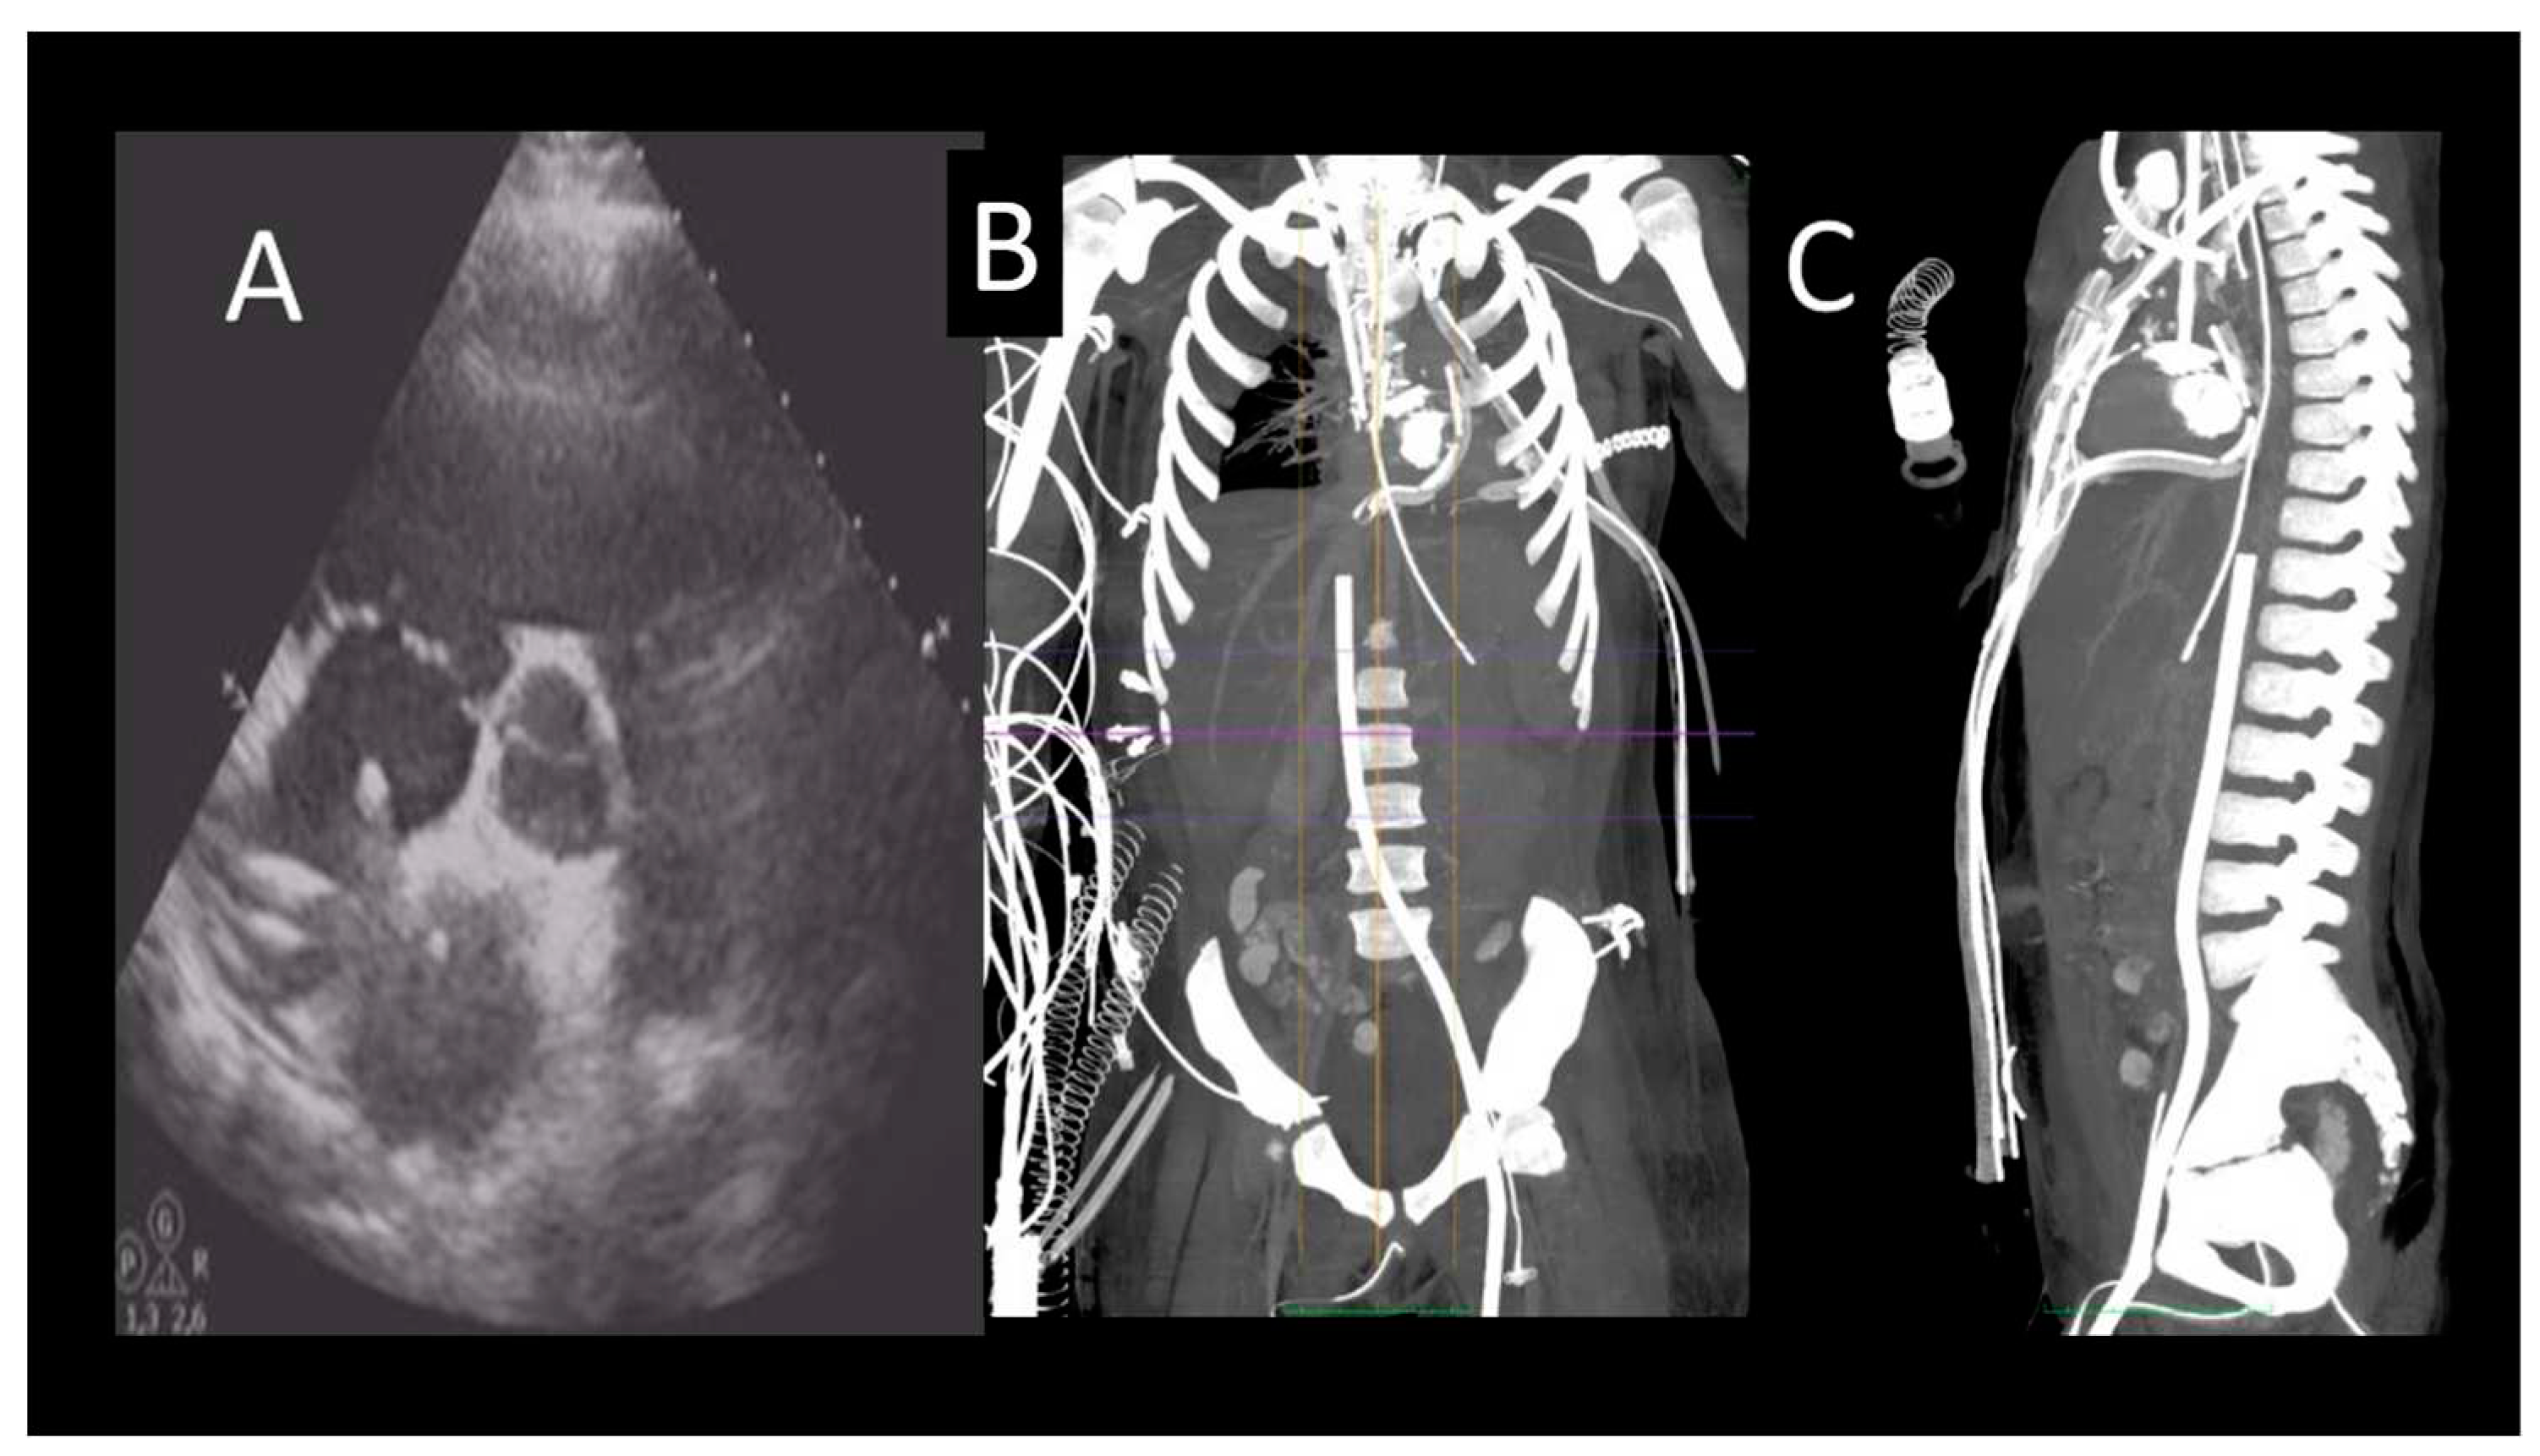

Figure 1. Representative case of use of CMR inf first acute heart failure. A, B) acute heart failure, CMR images showing severe LV dilatation, associated with hypertrabeculation. C) T2-weighet images exclude oedema; D- a diffuse endocardial late enhancement (red arrows) was detected, compatible with endomyoardial disease.

In ICM, LGE is transmural or subendocardial, while in a certain proportion of NICM, the presence of intramural or subepicardial LGE is detected. Notably, the absence of LGE does not completely exclude ICM in the case of hibernating myocardium (24). In ICM, an important role of CMR is the assessment of myocardial viability. The presence of scars extending more than 75% of the myocardial wall indicates a low probability of recovery after revascularization. On the other hand, the presence of scars affecting less than 25% of the myocardial wall indicates a good chance of recovery (24). In NICM, LGE has important prognostic implications in terms of site and distribution as its extent correlates to a major number of cardiovascular events. Examples of CMR findings are shown in Figure 1.